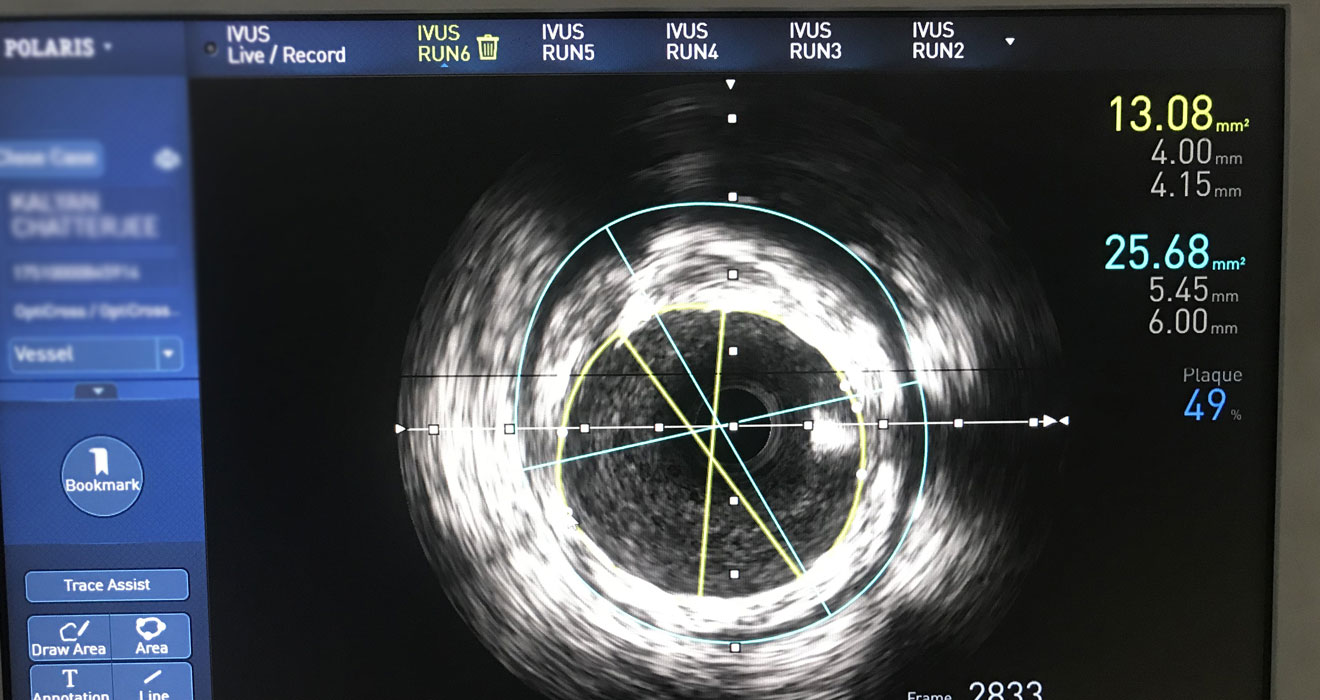

Intravascular Lithotripsy (IVL)

IVL uses sound waves to break down heavily calcified plaque within the arteries. This method is particularly beneficial for patients with severe calcification, as the sound waves help crack the plaque, making it easier to treat with a stent or balloon angioplasty. IVL offers a safe, gentle approach to tackling hard-to-treat coronary conditions.